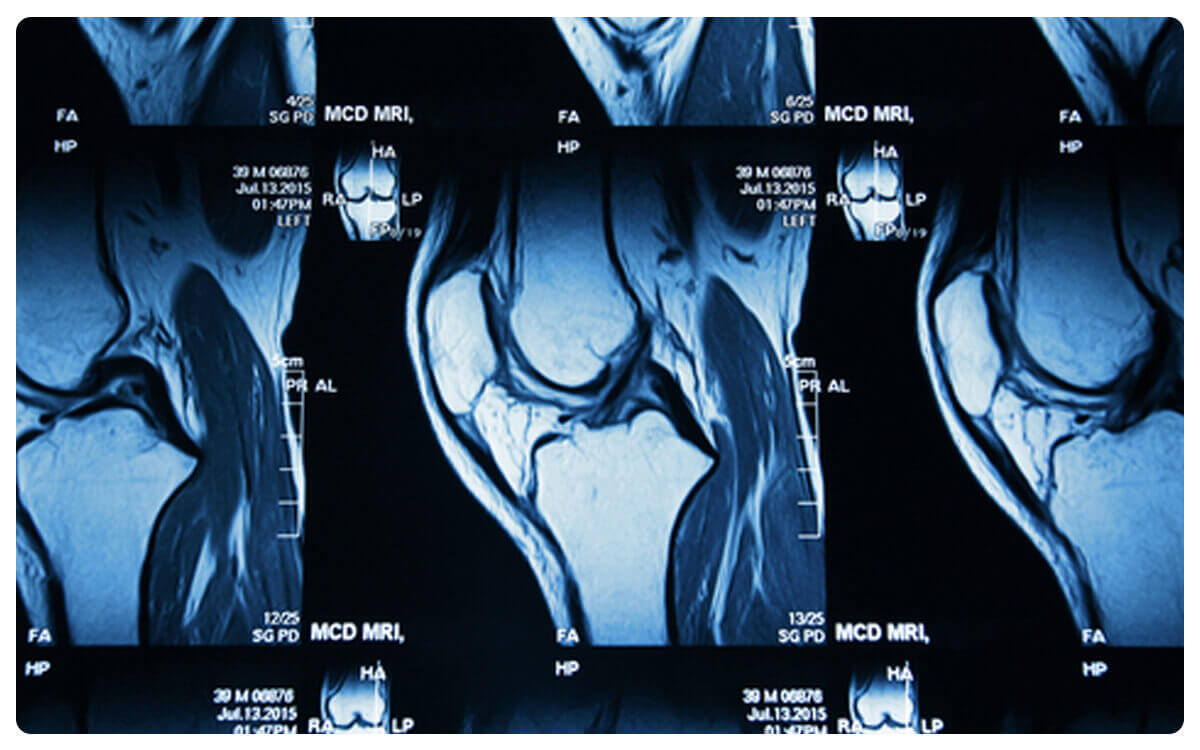

La Tomografía de Extremidad Inferior o Superior con Contraste, una técnica de imagen médica avanzada, se erige como una herramienta esencial en la evaluación detallada y precisa de las extremidades superiores e inferiores del cuerpo humano. A través de la tomografía computarizada y la administración de un medio de contraste intravenoso, esta técnica permite la obtención de imágenes tridimensionales de alta resolución que brindan una visión integral de huesos, músculos, vasos sanguíneos y posibles afecciones en estas áreas.

La Tomografía de Extremidad Inferior o Superior con Contraste desempeña un papel crucial en el diagnóstico y seguimiento de enfermedades musculoesqueléticas, trastornos vasculares y otras patologías, proporcionando información valiosa para la detección temprana de anomalías y la toma de decisiones clínicas informadas en el cuidado integral de la salud de las extremidades.